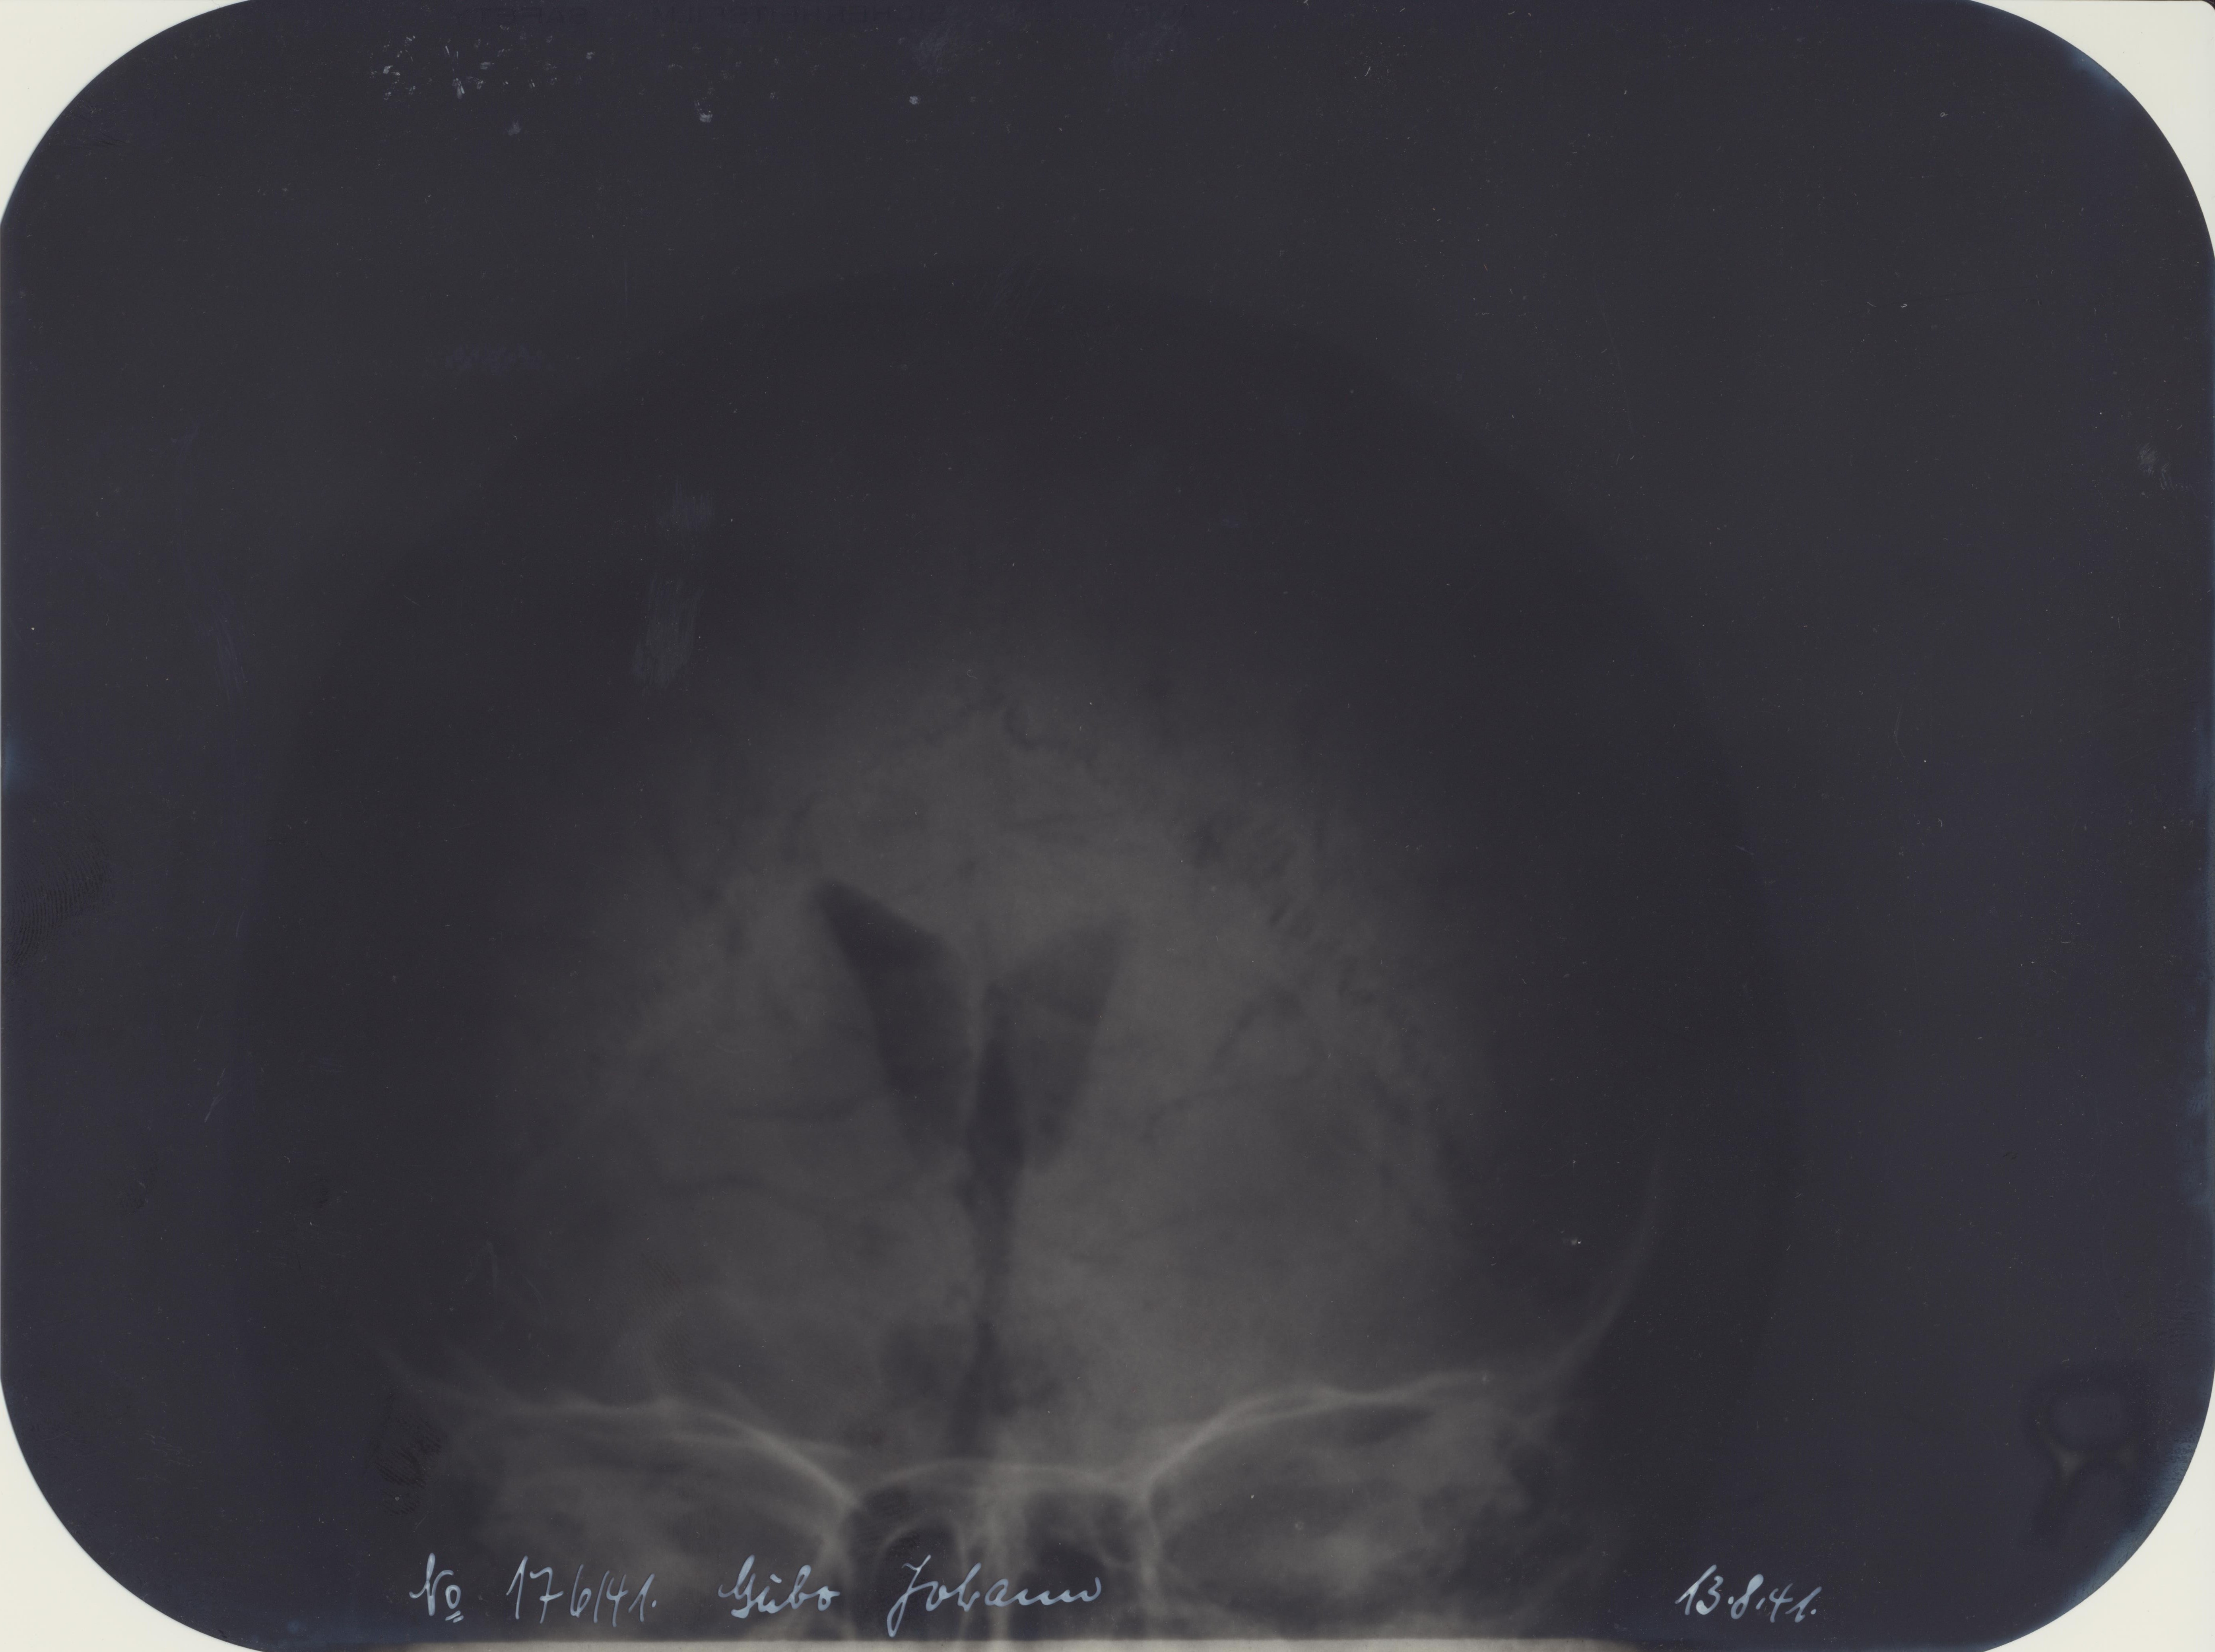

X-ray pictures Waffen-SS - Cubo Johann - 13.8.41